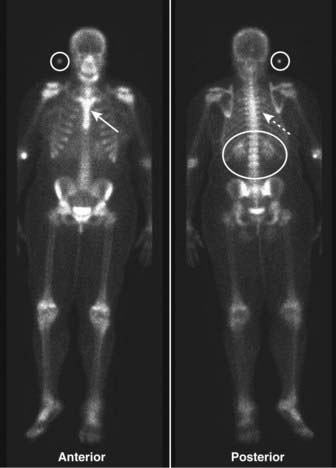

image Unlike the convention used for viewing other studies in radiology, the patient’s right side is not always on your left in nuclear scans. This can be confusing, so make sure you look for the labels on the scan (Fig. 1).

image

Figure 1 Normal bone scan.

Anterior and posterior views are frequently obtained, since each view brings different structures closer to the gamma camera for optimum imaging, e.g., the sternum on the anterior view (solid white arrow) and the spine on the posterior view (dotted white arrow). Notice that the kidneys are normally visible on the posterior view (white oval). Unlike the convention used in viewing other studies in radiology, the patient’s right side is not always on your left. On posterior views, the patient’s right side is on your right. This can be confusing, so make sure you look for the labels on the scan. In many cases a white marker dot will be located on the patient’s right side (white circles).